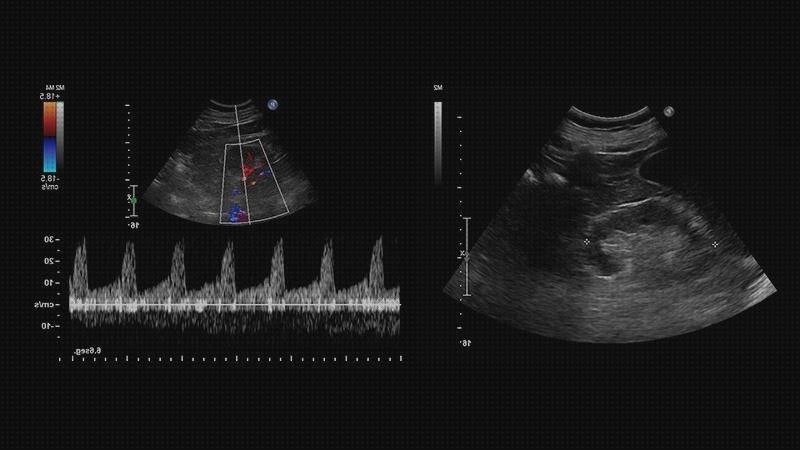

Ecografía doppler arterial de extremidades

Este estudio hace uso de ultrasonido para analizar el flujo sanguíneo en las arterias grandes de brazos y piernas. El ultrasonido no hace uso de irradiación ionizante y no está teniendo producto nocivos conocidos.

A veces, puedes precisar una arteriografía posteriormente. El examen se hace para contribuir a establecer arterioesclerosis de brazos o piernas; coágulo de sangre (coágulo) o para seguir una reconstrucción de las arterias con injertos (desviar).

Para la mayoría de los exámenes por ultrasonido, se ubica al enfermo tumbado boca arriba dentro de un camilla que puede doblar o desplazarse. Se podría solicitar que el paciente se mueva hacia ciertas lados para enriquecer la calidad de las fotos.

En la región a explorar se va a aplicar un gel para apoyar a que el transductor haga contacto en forma fiable con el cuerpo. Luego el radiólogo presionará el transductor con firmeza contra la piel en diferentes sitios, recorriendo el área de interés o modificando el ángulo del haz de audio desde un espacio al otro para vigilar mejor.